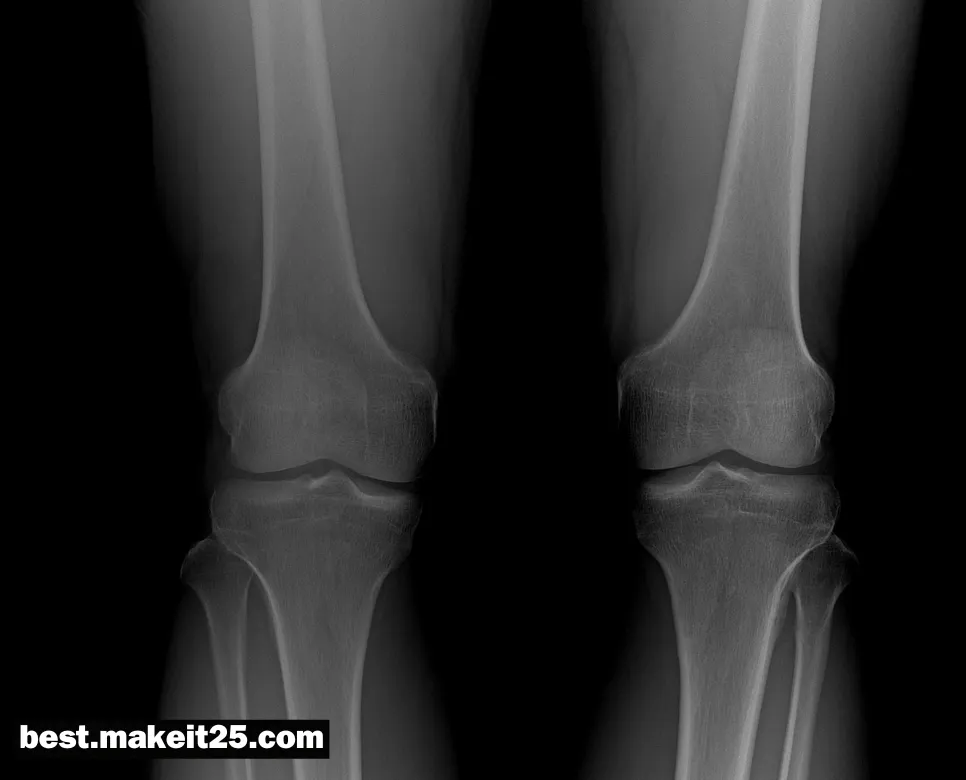

AP는 의학에서 자주 사용되는 용어로, “Anteroposterior”의 약자입니다. 이는 해부학적 위치를 나타내는 용어로, 신체의 앞쪽(Anterior)에서 뒤쪽(Posterior)으로의 방향을 의미합니다. AP는 주로 영상의학 분야에서 X-ray, CT, MRI 등의 영상을 판독할 때 사용됩니다.

- X-ray나 CT, MRI 등의 영상의학 검사에서 신체의 앞쪽에서 뒤쪽 방향으로 촬영한 영상을 지칭할 때 사용됩니다. 예를 들어, “Chest AP view”는 흉부의 앞쪽에서 뒤쪽으로 촬영한 영상을 의미합니다.

이렇게 AP는 의학 분야에서 다양한 의미로 사용되지만, 가장 대표적인 용법은 해부학적 위치를 나타내거나 영상의학 검사에서 촬영 방향을 설명할 때 사용되는 것입니다. AP 방향은 신체의 앞쪽에서 뒤쪽을 향하는 방향을 의미하며, 이는 의학 분야에서 정확한 위치 파악과 소통을 위해 매우 중요한 개념입니다.